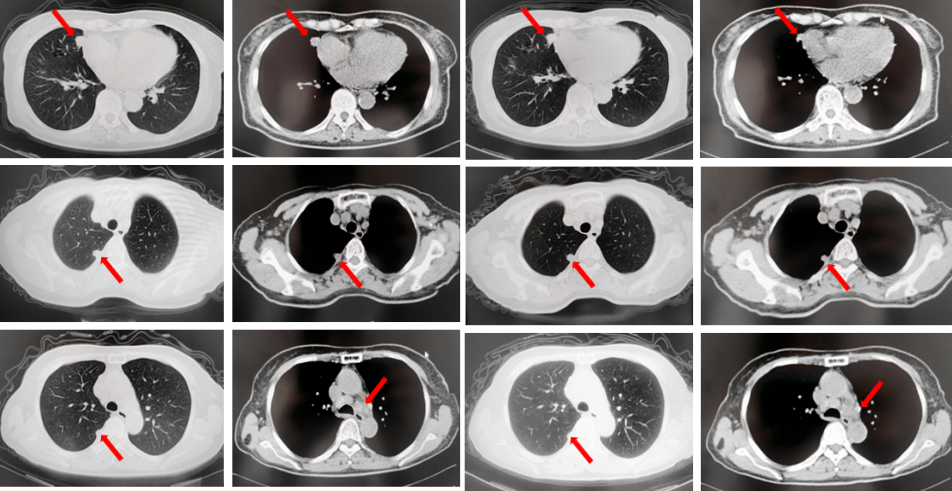

2022年7月至2022年11月行贝伐珠单抗联合培美曲塞/顺铂方案治疗6周期,2周期后评效PR,4周期后评效SD-(如图1)。第6周期治疗结束后患者自行终止治疗。

图1:由左至右分别展示基线(A.)及一线治疗后改变(B.和C.)。红色箭头指示病灶位置,由上至下分别为右肺肿物、右侧胸膜转移病灶及胸腔积液、左侧胸膜转移病灶、多发纵隔淋巴结肿大。

2023年3月患者因咳嗽伴胸闷复查出现全面PD。2023年3月-2023年4月重启原方案贝伐珠单抗联合培美曲塞/顺铂治疗2周期。2023年5月复查评效PD。行左锁骨上淋巴结穿刺,病理回报:左锁骨上见异型细胞,考虑为癌可能性大。组织NGS基因检测:MET基因扩增(变异倍数)2.0倍,TP53错义突变,PD-L1(22C3):TPS 75%。2023年5月-2023年8月改行替雷利珠单抗联合紫杉醇脂质体治疗4周期,2周期后评效SD。(如图2)

图2:A.代表一线治疗停药后病情进展,右肺上叶肿物、右侧胸膜转移灶及纵隔淋巴结较前增大、增多,右侧胸腔积液较前增多;B.原方案重启后复查评效右肺上叶肿物及纵隔淋巴结较前略饱满,右侧胸腔积液较前明显增多;C.更改二线治疗方案后整体病灶较前无显著变化。